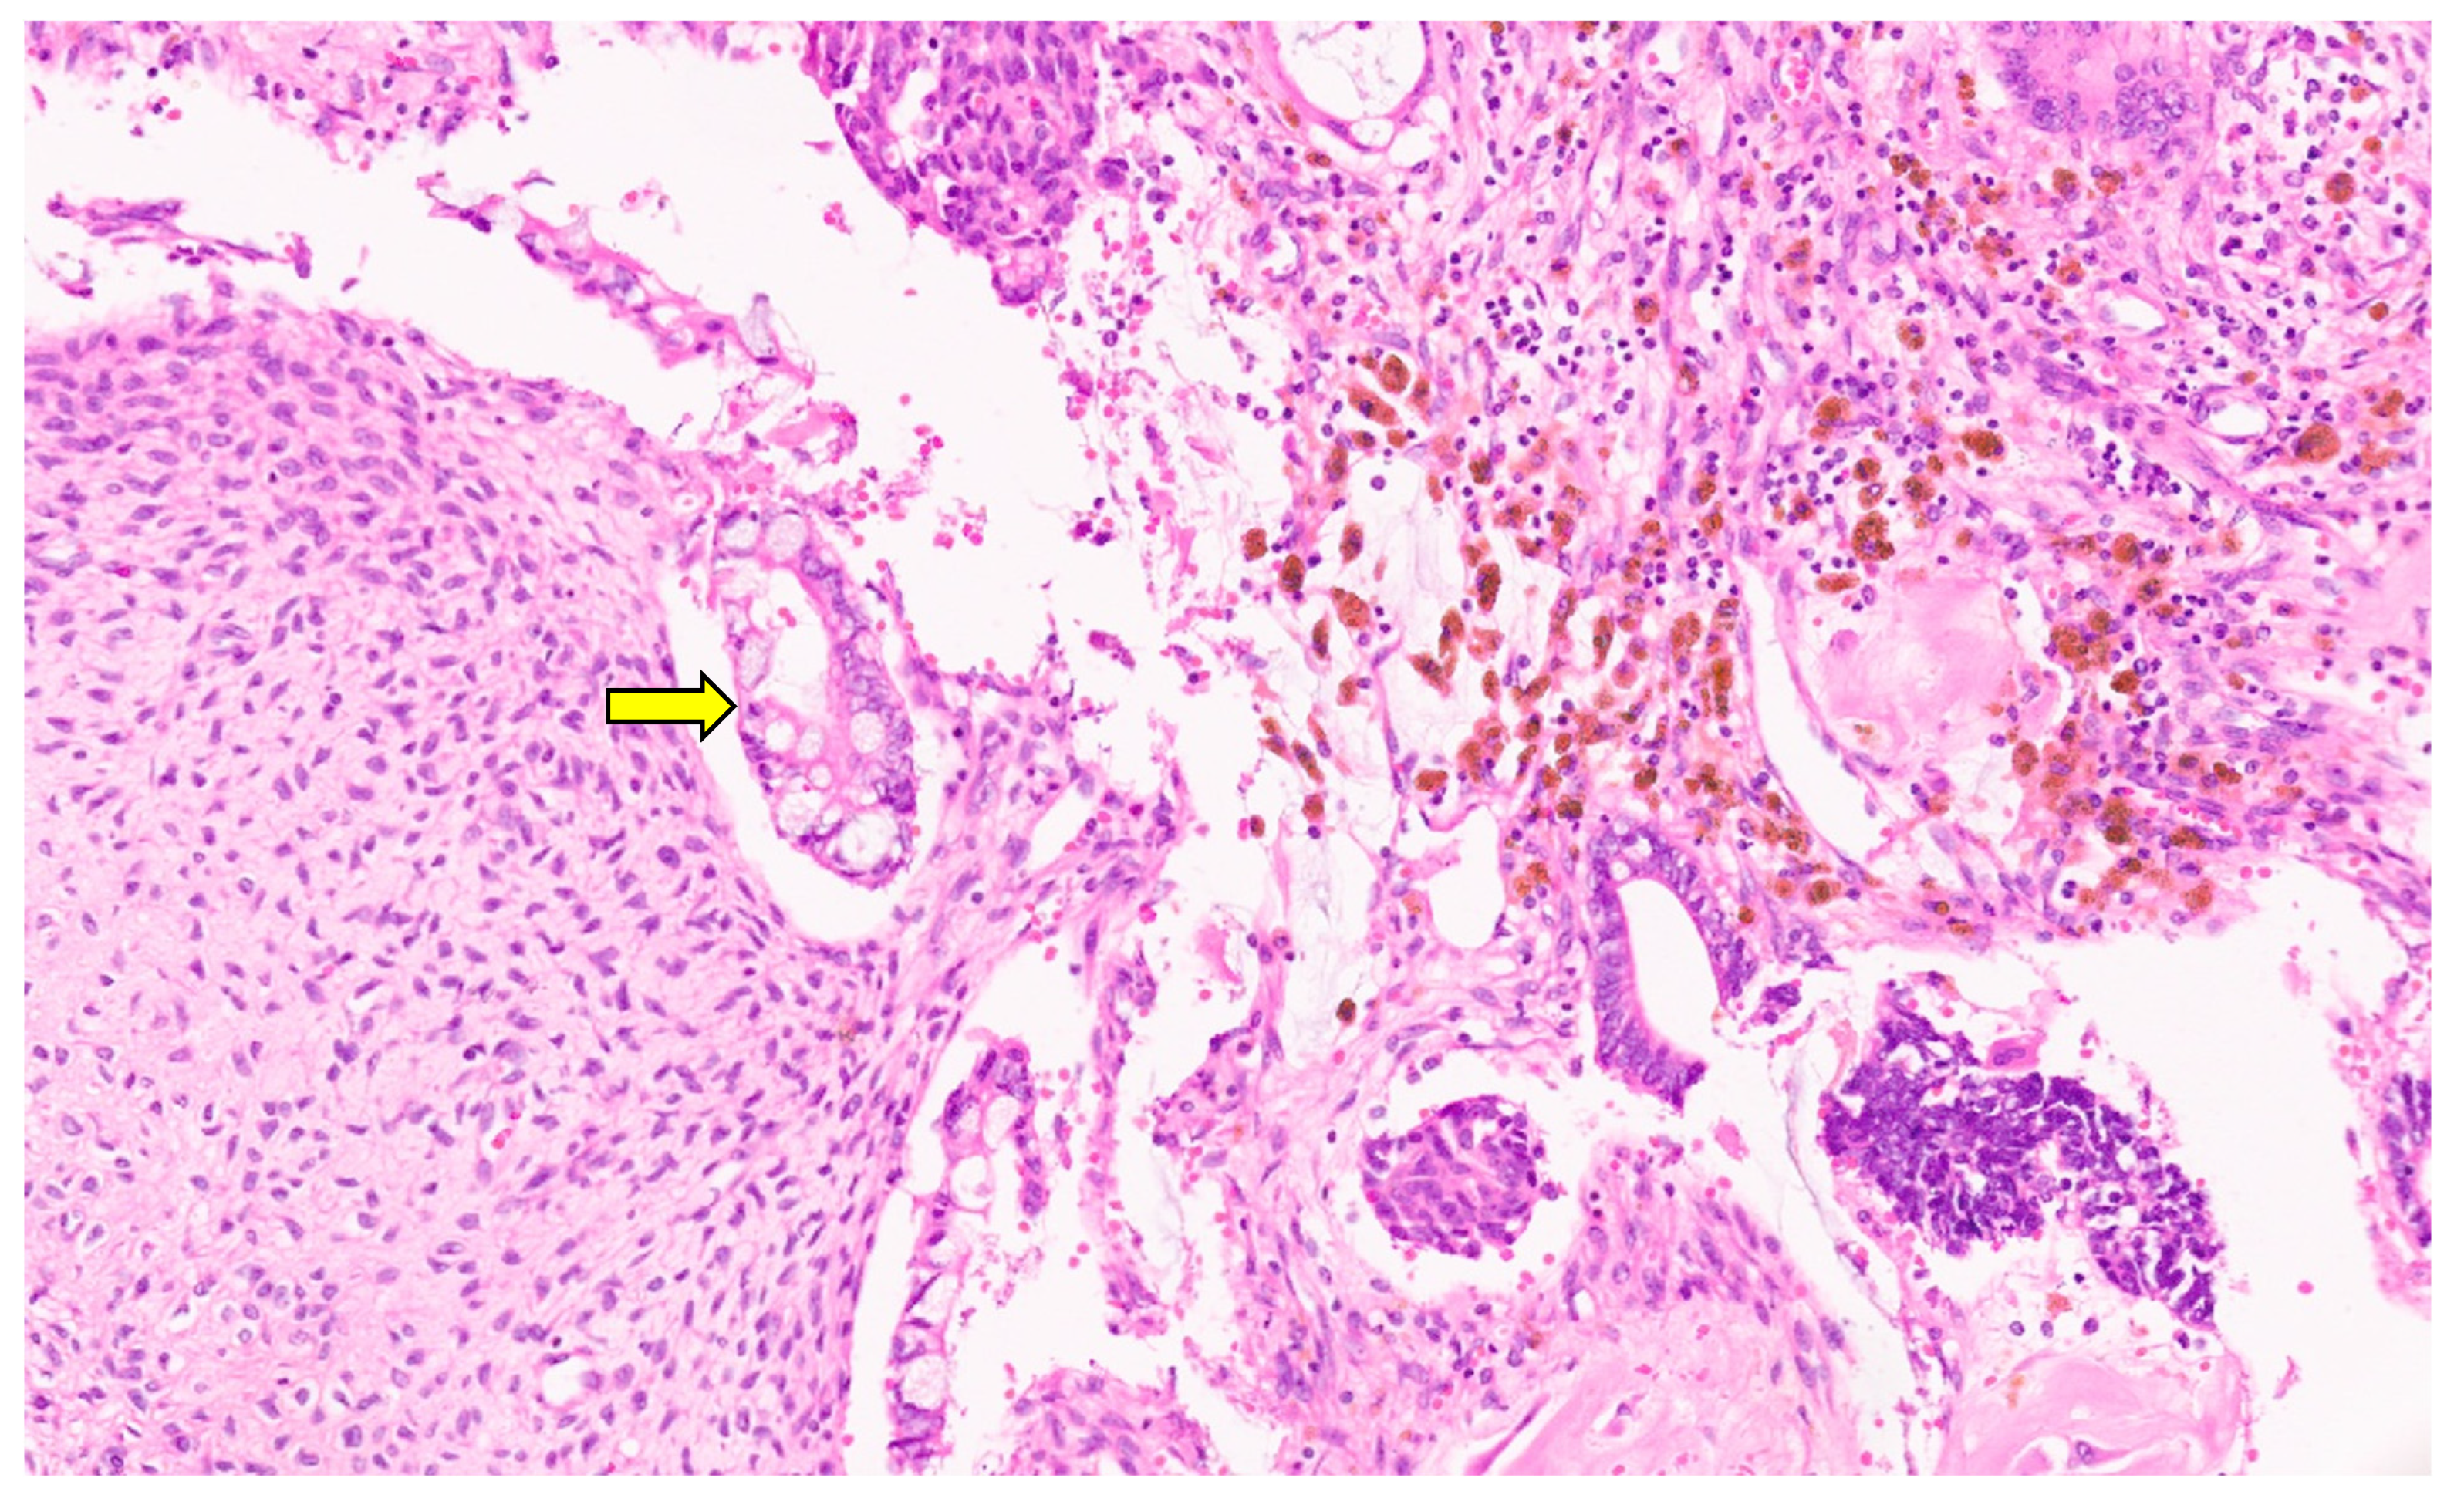

6.3. Pathology

10.3. Pathology